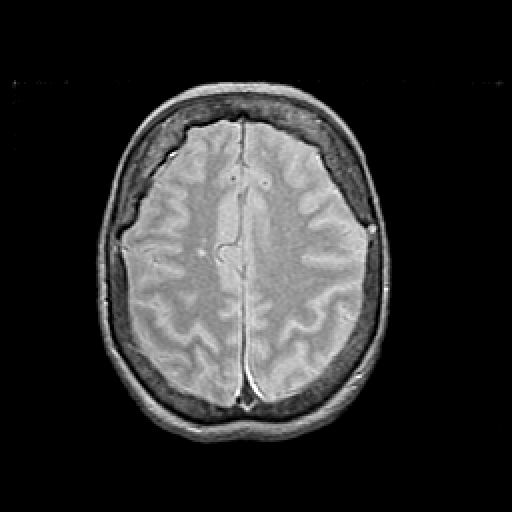

Proton density-weighted structural MR: Slice 39

Slice 39